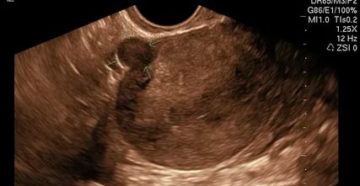

Когда и на какой день цикла делают УЗИ матки и придатков: показания и подготовка Женское…

Узи после месячных – когда проводить, почему существуют ограничения УЗИ после месячных проводят с целью…